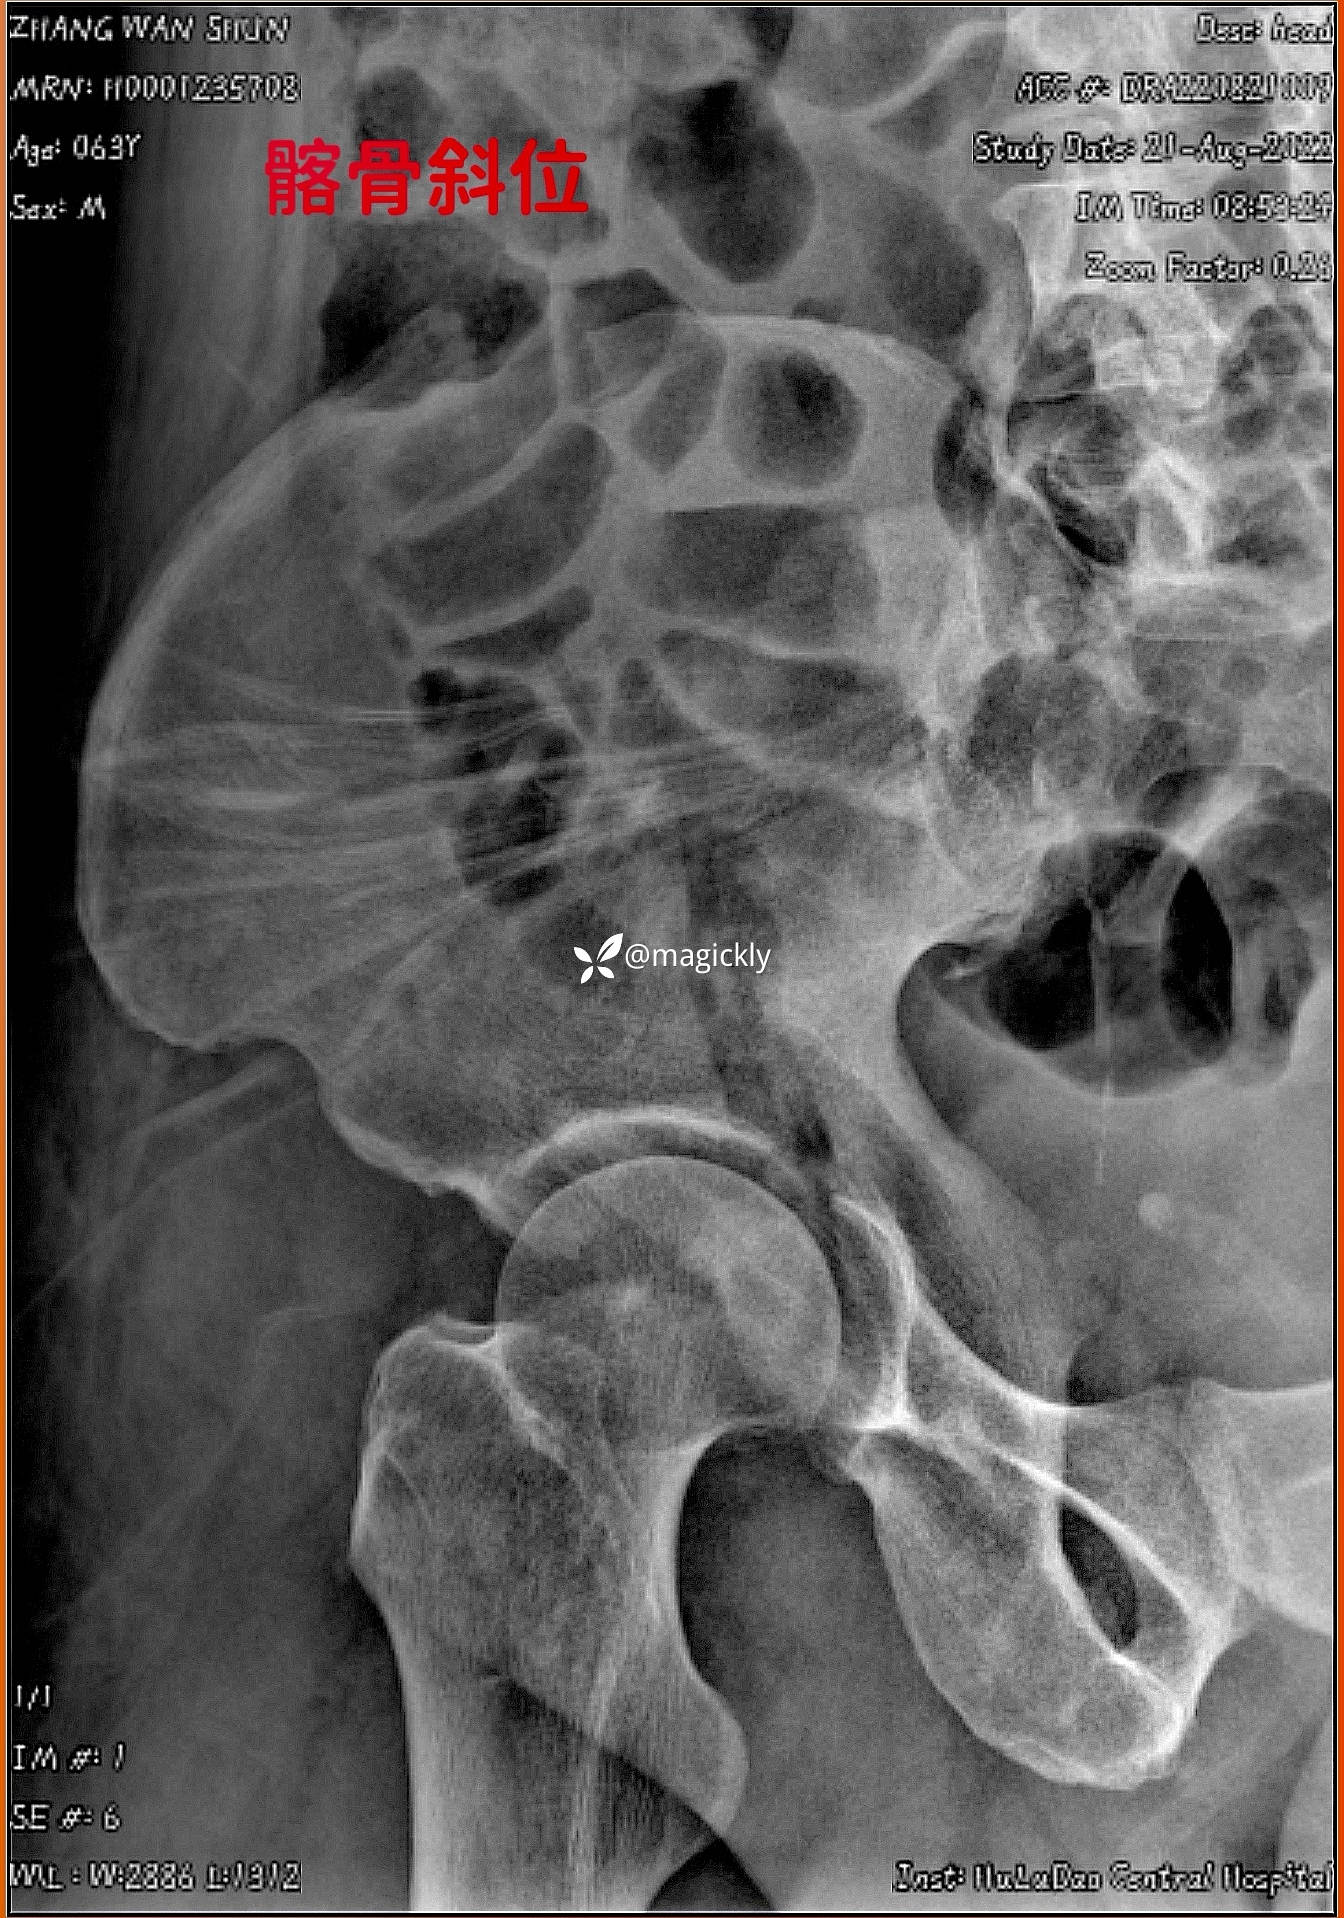

【检查】:局部体征明确,影像学结果如下

img

【临床诊断】:髋臼骨折(后上壁)